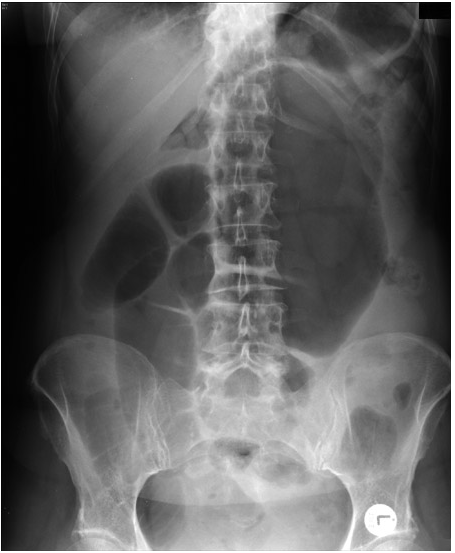

What does this X-ray show

Large bowel obstruction

Note

• dilation of the caecem >9cm is abnormal

• dilation of any other part of the colon >6cm is abnormal

• abdominal X-ray may demonstrate the level of obstruction

• abdominal x-ray cannot reliable differentiate mechanical obstruction from psuedo-obstruction

X-ray

• colon is dilated down to the level of the distal colon

• Soft tissue density at level of obstruction

• small volumen of gas has reached the rectum (obstruction no definite)